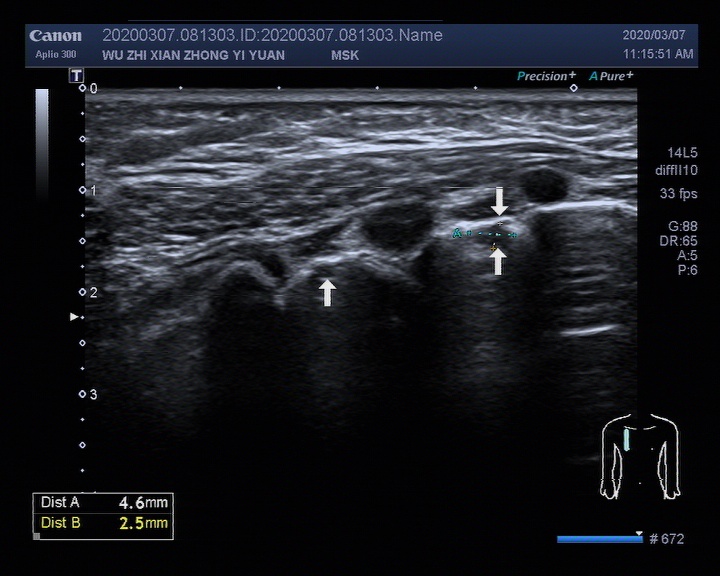

▎5个月婴儿肺脏超声检查超声图像

image009

白色箭头所示:右锁骨中线2-4肋间可见散在片状实性低回声结节,较大的约4.6x2.5mm,局部A线显示不清,2-5肋间可探及散在B线。